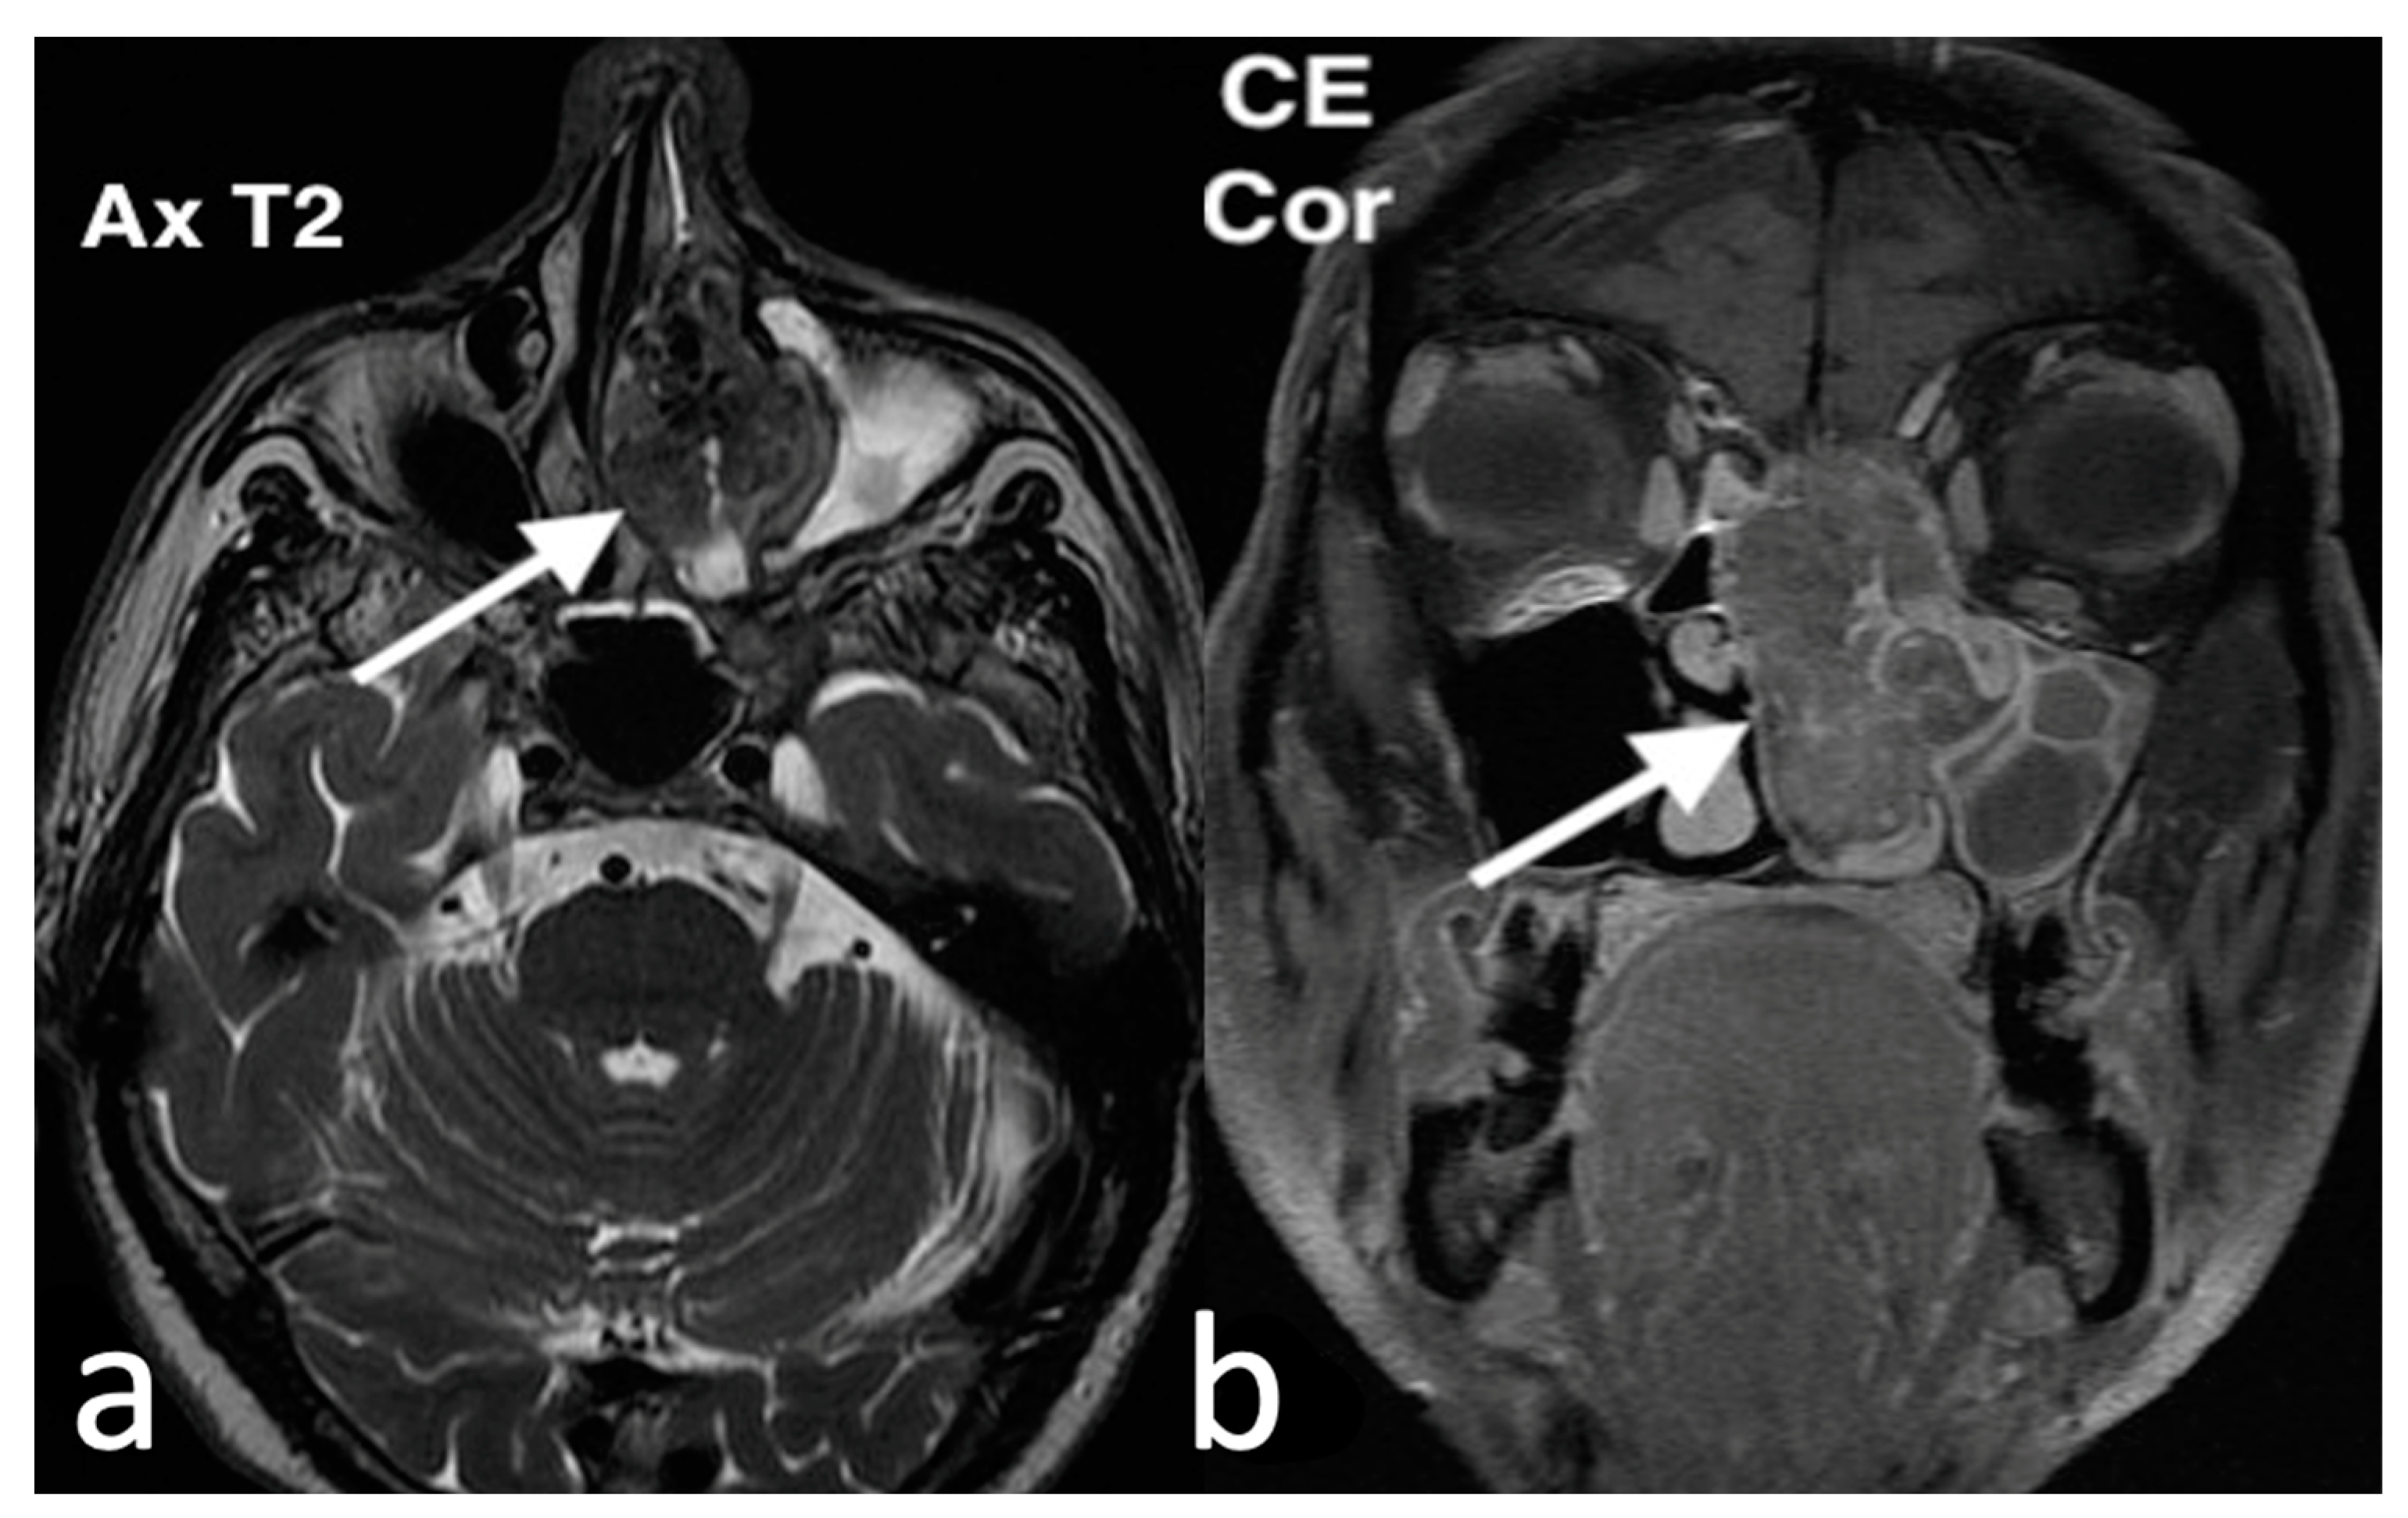

3.2.10. Sinonasal Tract Angiofibroma

3.3. Malignant Neoplasms